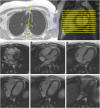

This document is an update to the 2013 publication of the Society for Cardiovascular Magnetic Resonance (SCMR) Board of Trustees Task Force on Standardized Protocols. Concurrent with this publication, 3 additional task forces will publish documents that should be referred to in conjunction with the present document. The first is a document on the Clinical Indications for CMR, an update of the 2004 document. The second task force will be updating the document on Reporting published by that SCMR Task Force in 2010. The 3rd task force will be updating the 2013 document on Post-Processing. All protocols relative to congenital heart disease are covered in a separate document.The section on general principles and techniques has been expanded as more of the techniques common to CMR have been standardized. A section on imaging in patients with devices has been added as this is increasingly seen in day-to-day clinical practice. The authors hope that this document continues to standardize and simplify the patient-based approach to clinical CMR. It will be updated at regular intervals as the field of CMR advances.